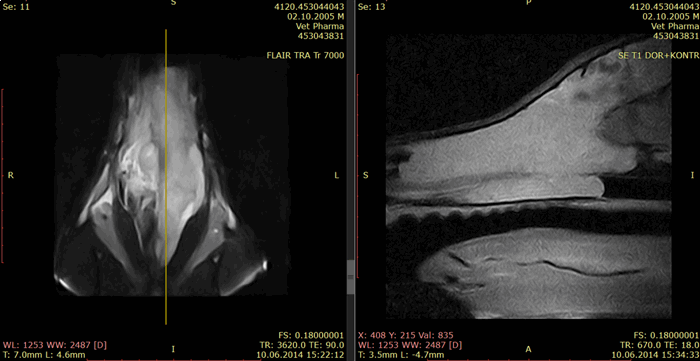

Магнитно-резонансная томография или компьютерная томография носовых ходов и придаточных пазух считаются золотым стандартом визуальной диагностики опухолей носовой полости. Для планирования лечения необходимо определить локализацию новообразования.

Объем новообразования и размер перифокального отека имеют значение для прогноза. Оценить по компьютерной томографии такие параметры, как размер новообразования и отек вокруг опухоли, нельзя.

Рис. 4. Программа FLAIR. Перифокальный отек обозначен стрелками, при этом объем новообразования на следующем рисунке 5 гораздо меньше (обозначено стрелками).

Рис. 5. Программа T1 с контрастом.